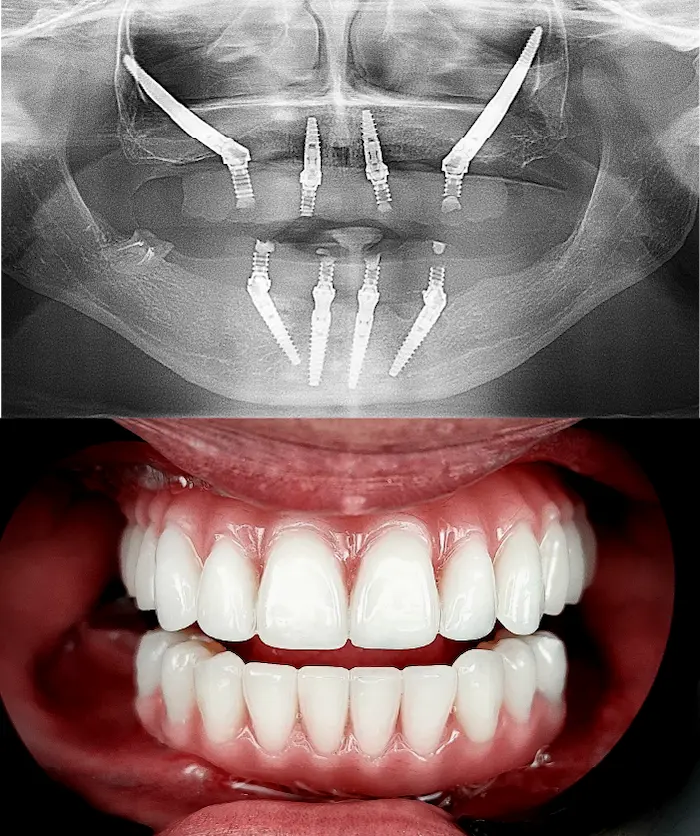

La soluzione di implantologia d’avanguardia quando non è possibile inserire impianti All-on o impianti zigomatici.

Gli impianti sottoperiostei (o impianti subperiostali) vengono creati su misura, in titanio puro T4 completamente biocompatibile, e applicati sulla superficie dell’osso residuo.

Sono progettati digitalmente per adattarsi alla tua anatomia in presenza di atrofia ossea severa.

Soluzione di implantologia avanzata indicata in casi di atrofia dell’arcata superiore, quando gli impianti tradizionali o l’All-On non sono utilizzabili.

Gli impianti dentali zigomatici fissi sono impianti in titanio lunghi 3 – 6 cm che si ancorano all’osso zigomatico, molto più denso e stabile dell’osso mascellare. In base alle necessità il chirurgo definirà se utilizzare un impianto Zygoma Quad (due impianti zigomatici per lato), Zygoma Hybrid oppure Zygoma Laterale.